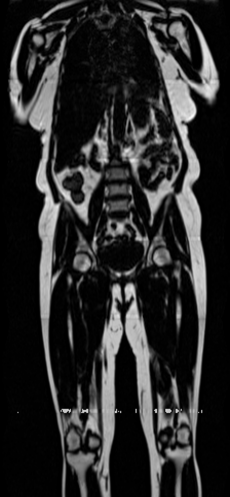

Preservation of Spine Curvature. For the spine segmentation on UK Biobank, we use a UNet++ model [81] with Dice Loss and use the curvature prediction of the spine followed in [9]). We measure the Pearson correlation factor [9] of spine curvature measured on the generated MRIs where the input is a single MRI coronal slice, or a single sagittal slice against the curvature of reference real MRIs of the same samples. The correlation coefficients are 0.89 for the coronal MRIs and 0.88 for the sagittal MRIs on the test set of 308 human-annotated angles.

B.3 Preservation of Spine Curvature and Fat

For the spine segmentation on UK Biobank, we use a UNet++ model [81] with Dice Loss. We use a model trained to predict curves on DXA on UK Biobank [9]. We show in Figure 20 that generated MRIs preserve the spine curvature from normal to severe scoliosis cases. We also study the case when DXA is used to generate the MRIs and show in Figure 14 how the correlation to real curvatures compares to the input MRI case. The curvatures of the MRI generated from the coronal plane match the DXA curvatures more than the curvatures generated from sagittal MRI. This is expected since the antero-posterior plane of DXA is equivalent to the coronal plane for MRIs. This also explains the greater Pearson’s correlation coefficient of the coronal MRI (0.89) and DXA-generated curvature (0.88) compared to sagittal-generated curvature (0.87) relative to the reference curvature on the coronal plane. We observe though that MRI generation using X-Diffusion from another plane than the conventional plane for scoliosis assessment is valid.

For the spine segmentation on UK Biobank, we use a UNet++ model [81] with Dice Loss. We use a model trained to predict curves on DXA on UK Biobank [9]). We measure the Pearson correlation factor [9] of spine curvature measured on the generated MRIs where the input is a single MRI coronal slice, a single sagittal slice, or from the paired DXA, against the curvature of reference real MRIs of the same samples. The correlation coefficients are 0.89 for the coronal MRIs, 0.88 for the sagittal MRIs, and 0.87 for the DXAs on the test set of 308 human-annotated angles. We can then bin the curvature, , of the spines under different scoliosis categories based on human-annotated angles: mild: , moderate: , and severe . We show the results in Figure 20. This illustrates that the generated MRIs preserve the spine curvature from normal to severe scoliosis cases.